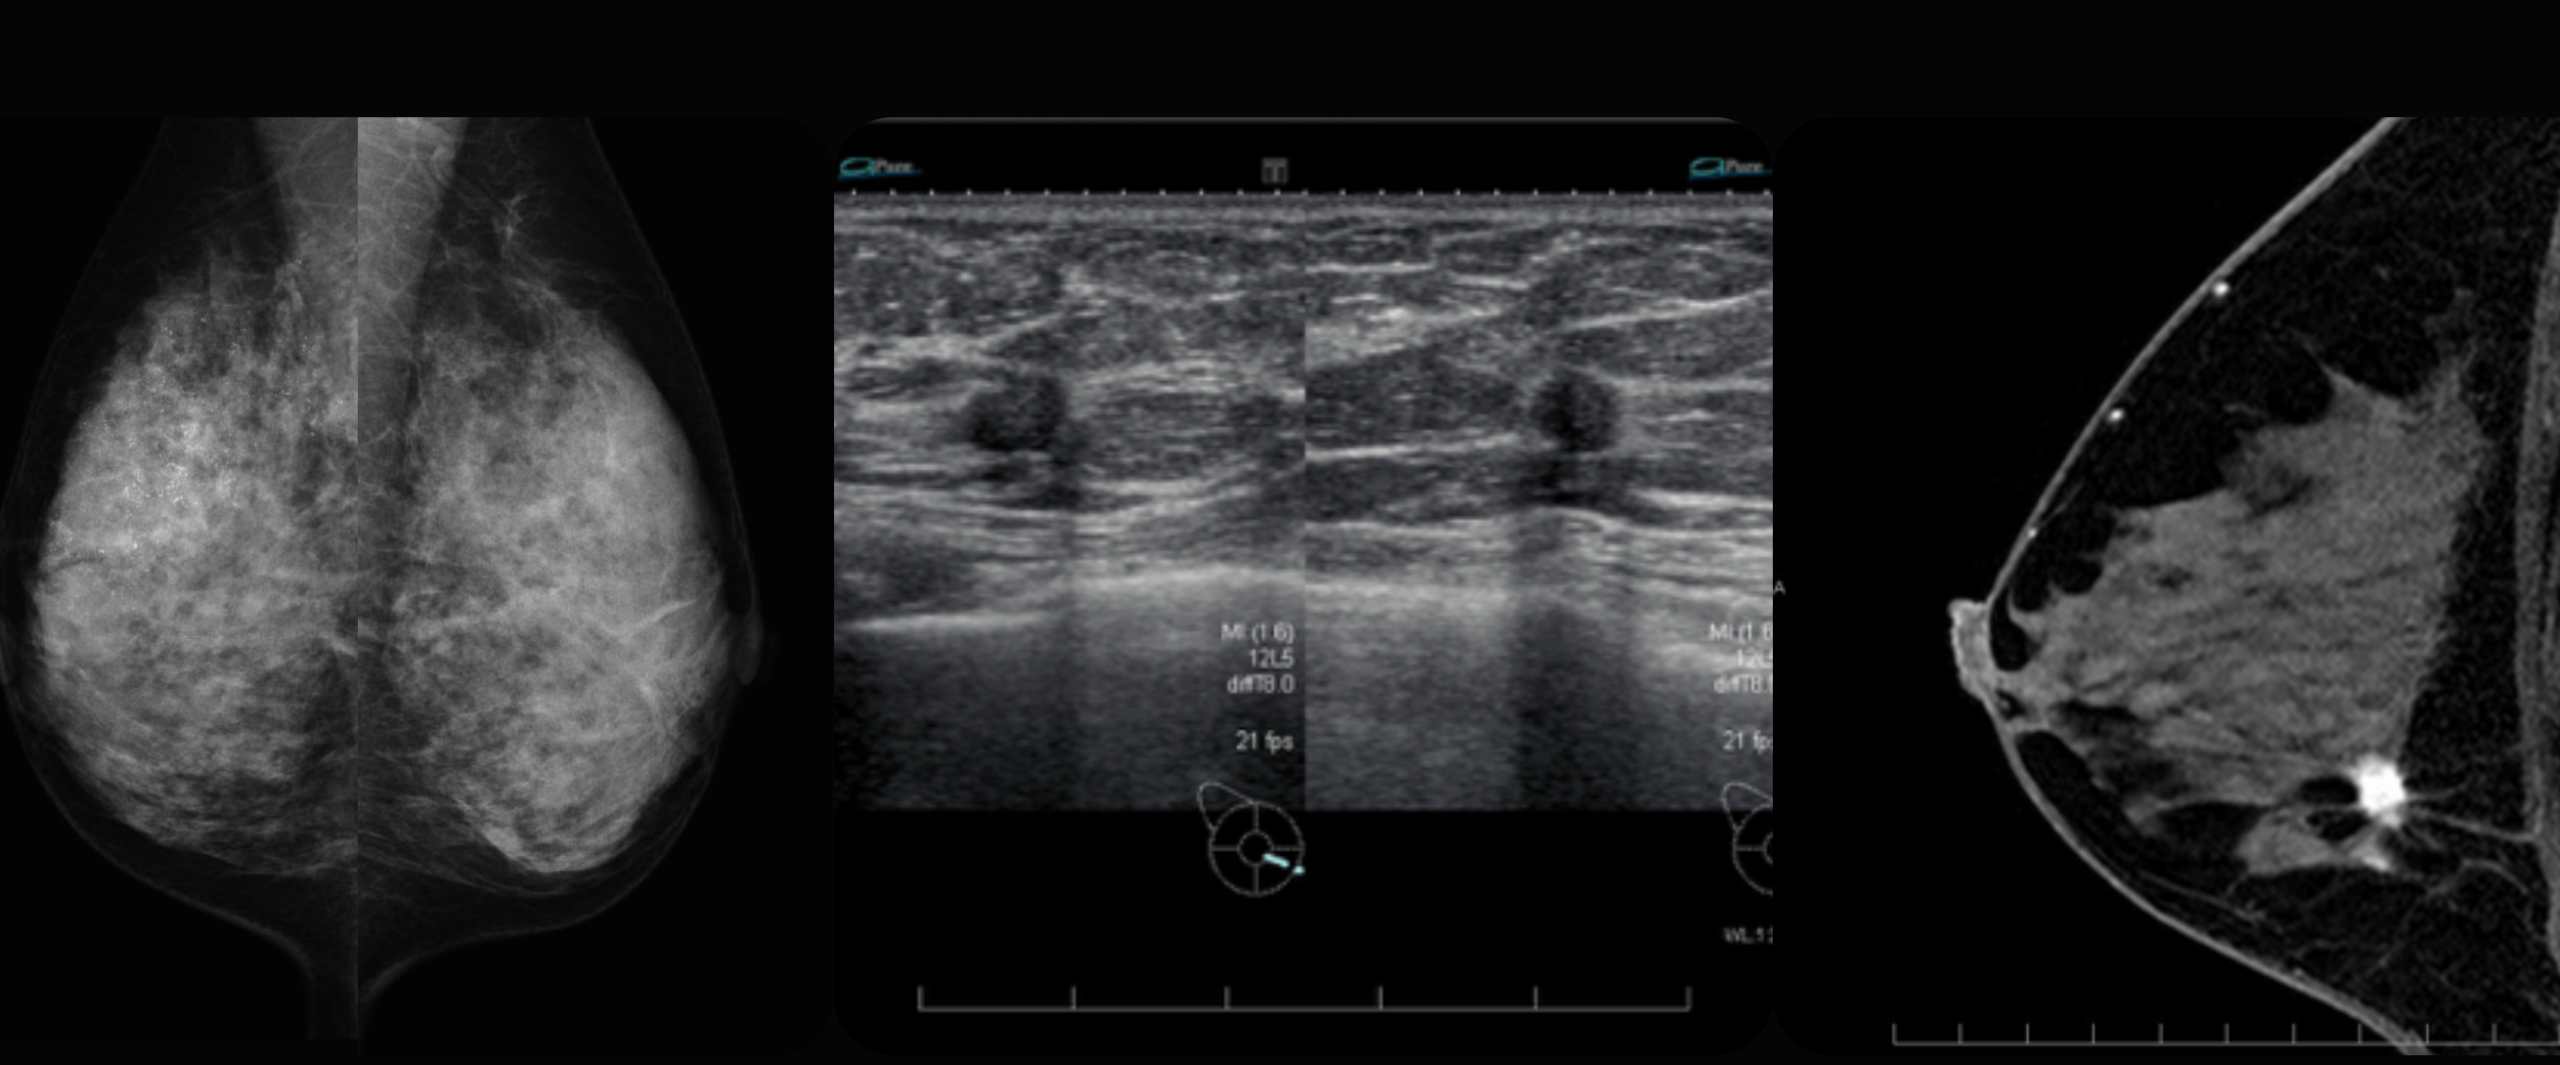

聖マリアンナ医科大学で10年以上、アメリカ HOLIGICでコンサルタントを務めるSatoko Foxが主催する乳腺画像を勉強会グループを2023年4月スタート。

留学後、アメリカで国際結婚をした私はHOLOGICでAI・画像読影コンサルタントとして仕事を再開し、現在は日本からの乳腺MRIの遠隔読影の仕事も請け負っており、全てのモダリティで乳腺の画像診断をしています。

グローバルスタンダードな乳腺の画像診断をわかりやすく

グローバルスタンダードな乳腺の画像診断をわかりやすく、元気にお教えします。

日本のエコー・MRI診断から、アメリカの最新AI画像診断まで。グローバルな情報をお届けします

聖マリアンナ医科大学/ 附属ブレスト&イメージングセンターで乳腺の画像診断の経験を積む

スタンフォード大学放射線科乳腺画像部門に研究留学

HOLOGICでトモシンセシスのAIプロジェクト(Genius AI Detection Technology)に参加

乳腺MRIの読影も遠隔で行っている